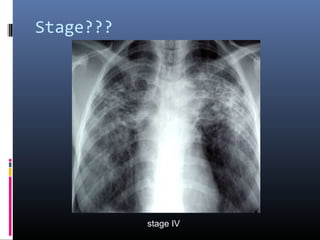

stage IV

• #16 typical chest film of long standing sarcoidosis (stage IV) with fibrosis in the upper zones and volume loss of the upper lobes resulting in hilar elevation. Fibrosis results in obliteration of pulmonary vessels, which can lead to pulmonary hypertension.

• #17 Stage IV pulmonary sarcoidosis in a 48-year-old man. (a) Chest CT scan (lung window) demonstrates traction bronchiectasis (arrowheads) and fibrotic lesions with extensive calcification, findings that indicate stage IV disease. (b) Chest CT scan (mediastinal window) demonstrates calcification in the fibrotic lesions, mediastinal adenopathy, and irregularly thickened pleura (arrowheads).

• #18 Stage IV pulmonary sarcoidosis in a 60-year-old man. Chest CT scan demonstrates extensive fibrotic change and cavitary lesions with a central distribution (arrows) that distort the lung parenchyma. Irregular thickening of the pleura (arrowheads) and overinflation of the peripheral lung parenchyma are also seen.